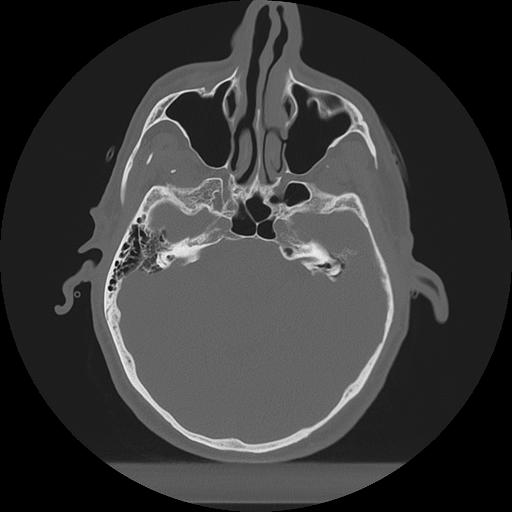

11 HUESO,,Axial,2.0,HUESO,,